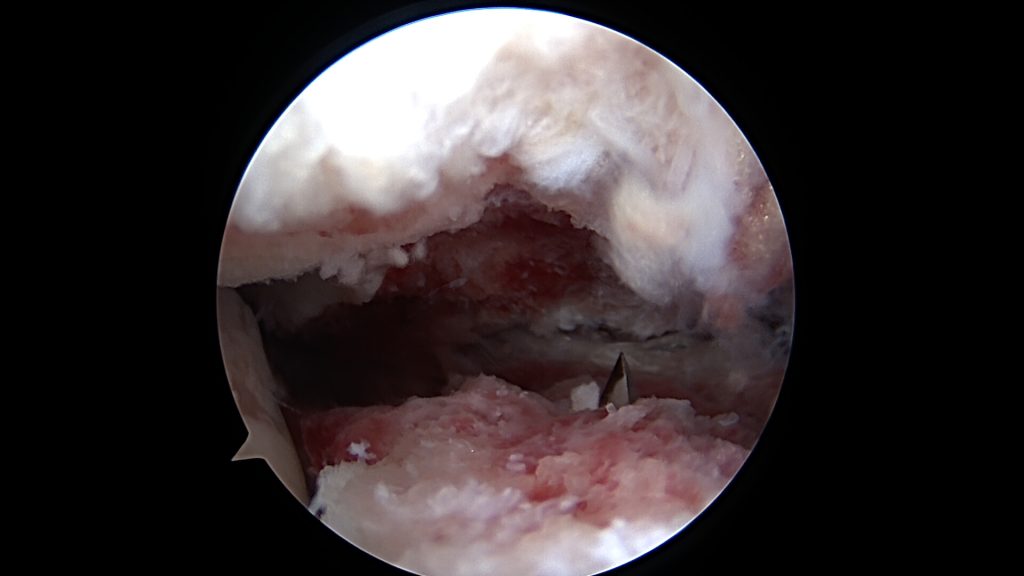

W tych przypadkach pomocne okazuje się zastosowanie artroskopii. W przypadkach złamań zakwalifikowanych do leczenia operacyjnego możemy w ten sposób usunąć z jamy stawu krwiak oraz wolne elementy kostne, które powstały podczas urazu. Inspekcja stawu przy pomocy artroskopu pozwala na dokładną ocenę powierzchni stawowych, ich ustawienie czy stwierdzenie ubytków. Dokonując repozycji odłamów (nastawiania złamania) możemy je dokładnie dopasować pod kontrolą wzroku, minimalizując w ten sposób powstanie nierówności. Bardzo ważne jest to podczas leczenia np. złamania kości skokowej, które w ten sposób możemy leczyć przezskórnie, bez wykonywania klasycznych cięć skóry. Sprawdzamy także stabilność zespolenia, czy fragmenty kostne są ze sobą trwale zespolone zastosowanymi śrubami czy płytami.